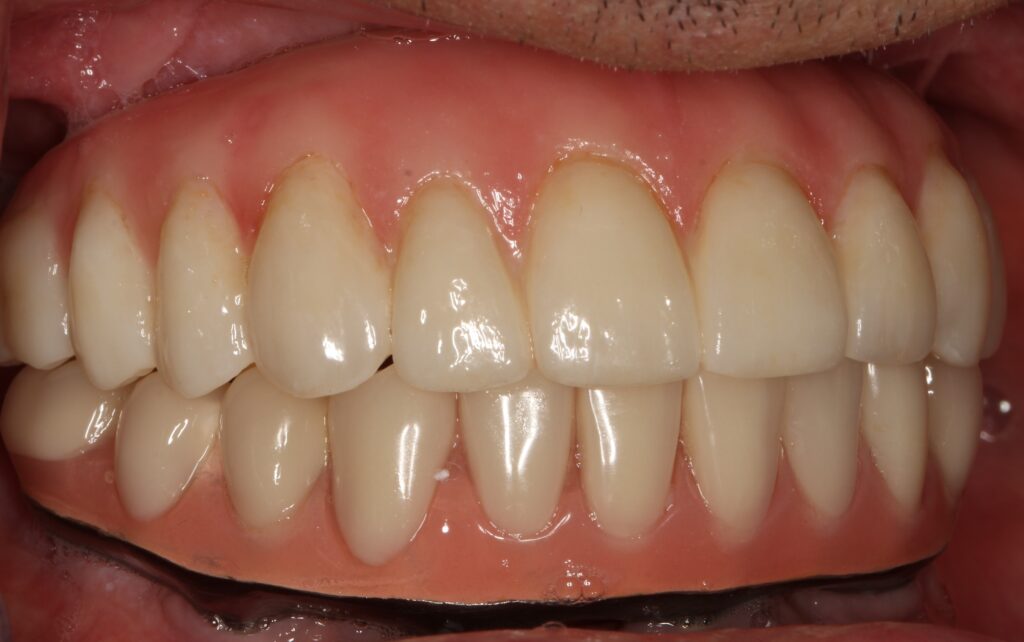

A selection of full arch fixed implant bridge patients after 5 years of wear